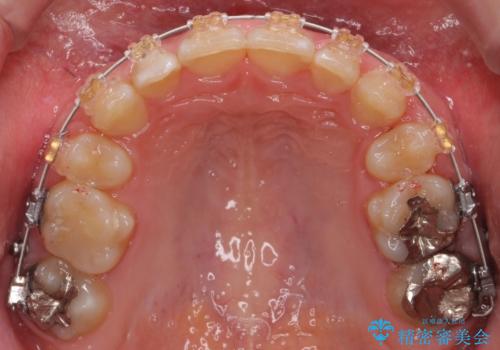

- 審美装置

奥歯のかみ合わせが、歯と歯が向かい合わせになっておりまた、歯ぎしりも多い方で装置の脱離も頻繁にありました。

ワイヤー矯正ではやや難しい症例でした。